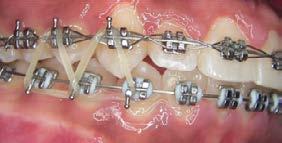

Tratamiento de caninos retenidos superiores en paciente en crecimiento con clase II división 2. Reporte de caso clínico

Los caninos retenidos constituyen una alteración eruptiva frecuente, con mayor prevalencia en la arcada superior. Su etiología es multifactorial y puede interferir con el trayecto normal de erupción, comprometiendo la oclusión y la estética.

Objetivo: Corregir una maloclusión Clase II división 2 mediante tratamiento ortodóntico en un paciente en crecimiento con ambos caninos superiores retenidos. Metodología: Se presenta el caso de un paciente masculino de 12 años, en dentición permanente, con perfil convexo, patrón dolicofacial y Clase II esquelética. Se realizó tratamiento ortodóntico sin extracciones. Para la tracción y alineación de los caninos retenidos se emplearon resortes abiertos (open coil springs) para la creación de espacio. Resultados: